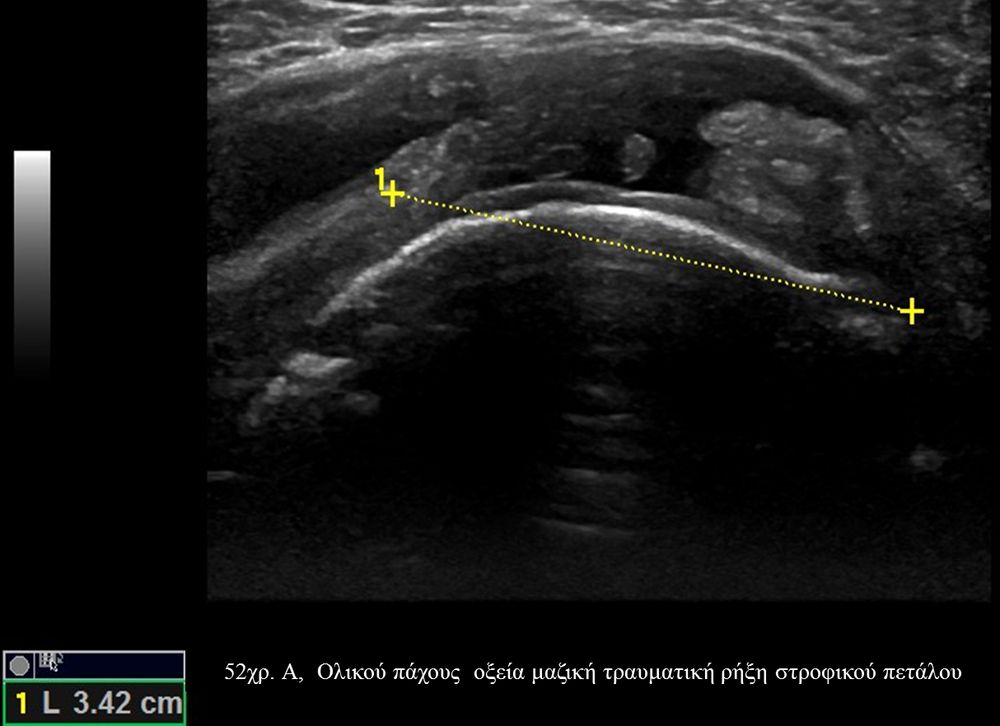

Είναι μια νέα μέθοδος που χρησιμοποιεί υψηλής ευκρίνειας υπερήχους για τη διάγνωση μυοσκελετικών παθήσεων που αφορούν τένοντες, μυς, συνδέσμους, νεύρα και περιφερικές αρθρώσεις. Η μέθοδος αναπτύχθηκε τα τελευταία χρόνια και αποτελεί αναπόσπαστο μέρος στη διαφορική διάγνωση παθήσεων που αφορούν τηνορθοπαιδική, αθλητιατρική, ρευματολογία και παιδιατρική.

Πρόκειται για υπερηχογράφημα υψηλής ευκρίνειας που επιτρέπει την λεπτομερέστατη απεικόνιση (σε επίπεδο χιλιοστού) ακόμη και πολύ μικρών/επιφανειακών ανατομικών δομών και απαιτεί ειδικό υπερηχογραφικό εξοπλισμό καθώς και εξειδίκευση του ακτινολόγου. Η εξέταση γίνεται με δυναμικό τρόπο, δηλ εκτελούνται δοκιμασίες κίνησης του μέλους που πάσχει, ώστε να αποκαλυφθεί η παθολογίαακόμη και όταν δεν είναι εμφανής σε θέση ηρεμίας. Επιπλέον, η εξέταση είναι ανώδυνη και ασφαλής και δεν περιλαμβάνει ακτινοβολία (CT), μαγνητικό πεδίο (MRI) ή παραμονή σε κλειστό χώρο και είναι πολύ ανεκτή τόσο σε ενήλικες όσο και σε παιδιά.

- Παθήσεις Ώμου (πχ ρήξη στροφικού πετάλου)